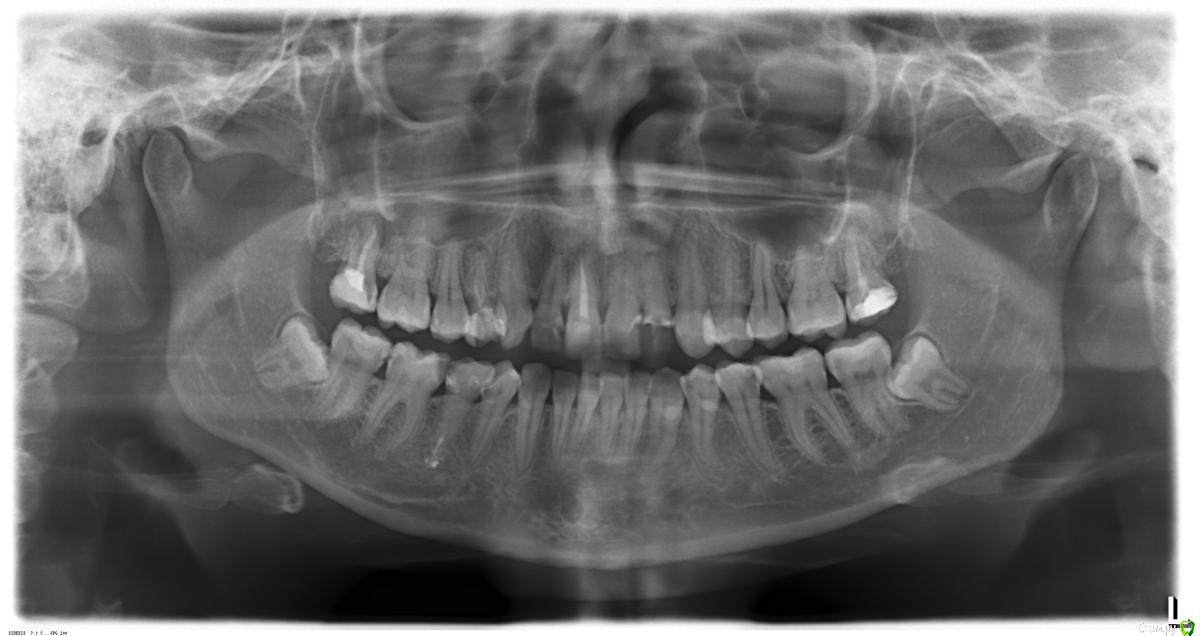

Хомячок Опубликовано 30 января, 2015 Поделиться Опубликовано 30 января, 2015 Добрый день! Очень прошу помощи, ситуация в следующем:Три года назад залечила много зубов в платной клинике. Зубы болели, лечила много.Сейчас эти же зубы начали один за другим болеть вновь. Пошла к другому врачу, вскрываем больной зуб,а там в каждом воспаление и киста. Ставили временную пломбу с лекарством, по пол года ходила меняла...Сейчас очень сильно (как никогда) заболела верхняя 7ка, тоже залеченная когда-то три года назад тем же "врачом". Доктор к которому в последнее время хожу не принимала в этот день, поэтому пошла в первую ближайшую клинику. Там мне сделали снимок, сказали "обострение хронического периодонтита, прикорневая киста, удалять". Решила не спешить удалять, пришла к своему врачу, она мне его вскрыла, оттуда пошел мерзкий запах и гной. Что-то там почистили, и так и оставили. Т.е. сейчас на зубе ничего нет, голая десна. Боль моя не уменьшилась, вот уже неделю живу на кетанове. Как только действие заканчивается, болит пол головы (висок, затылок, глаз...)В моем нынешнем враче меня смущает то, что по моим снимкам она не говорит мне что делать следующим, что перелечить, что полечить. Прихожу по факту-болит-лечим. А так чтобы увидеть и предотвратить - нет такого. Хотя, мне кажется, что перелечивать еще там очень много надо. Сейчас она мне сказала мол, посмотрим, если станет хуже - то удалять, а если нет то будем лечить как раньше (временная, менять, и тд) Мне хуже не стало, ничего не раздуло и тп, но болит все так же невыносимо. Помогите, что мне сейчас делать? Вырывать 7ку?Я слышала такое мнение, что если удалять зуб, то на его место надо обязательно что-то ставить, иначе остальные зубы "лягут" или "поедут". Правда ли это или у всех по-разному? Дело в том, что у меня сахарный диабет 1-го типа, скорее всего мне нельзя ставить имплантаты? (Диабету 7 лет, мне 25) Помогите, пожалуйста. Прошу прощения, что много написала, но я уже не могу, плачу каждый день. 25 лет, а зубы как у старого деда(((( 1 Ссылка на комментарий

red_butler Опубликовано 31 января, 2015 Поделиться Опубликовано 31 января, 2015 Какой из седьмых зубов беспокоит? Снимок сделан уже после последнего лечения зуба? Ссылка на комментарий

Хомячок Опубликовано 31 января, 2015 Автор Поделиться Опубликовано 31 января, 2015 Какой из седьмых зубов беспокоит? Снимок сделан уже после последнего лечения зуба?Беспокоит тот, что у меня находится наверху справа. На снимке, как понимаю, он наверху слева. (если что простите, я чайник). Снимок сделан до того, как мне его вскрыли, со старой пломбой трехлетней давности. Сейчас он у меня открыт и болит(Еще беспокоит 4ка, которая у меня наверху справа, ( На снимке там временная пломба, сейчас он тоже вскрытый и там ничего нет, болит(( Ссылка на комментарий

IvanK Опубликовано 31 января, 2015 Поделиться Опубликовано 31 января, 2015 нужен новый снимок, (после лечения) - прицельный, в идеале кт Сейчас он у меня открыт это очень плохо Ищите хорошего терапевта... Ссылка на комментарий

IvanK Опубликовано 31 января, 2015 Поделиться Опубликовано 31 января, 2015 8ки нужно удалить Ссылка на комментарий

Хомячок Опубликовано 31 января, 2015 Автор Поделиться Опубликовано 31 января, 2015 нужен новый снимок, (после лечения) - прицельный, в идеале кт Просто именно после этого снимка меня отправили на удаление в ЧЛХ в 1ый мед. Типа там киста, которая уходит в гайморову пазуху. Т.е. они даже его не трогали, сразу удалять. После этого другой врач зуб вскрыла, распломбировала (?), промыла. Нужен теперь новый снимок? Я сделаю. Если можно, подскажите где в Спб сделать эту комп.томограмму?Я правильно понимаю, что по этому снимку нельзя однозначно сказать что зуб надо удалять? Ссылка на комментарий